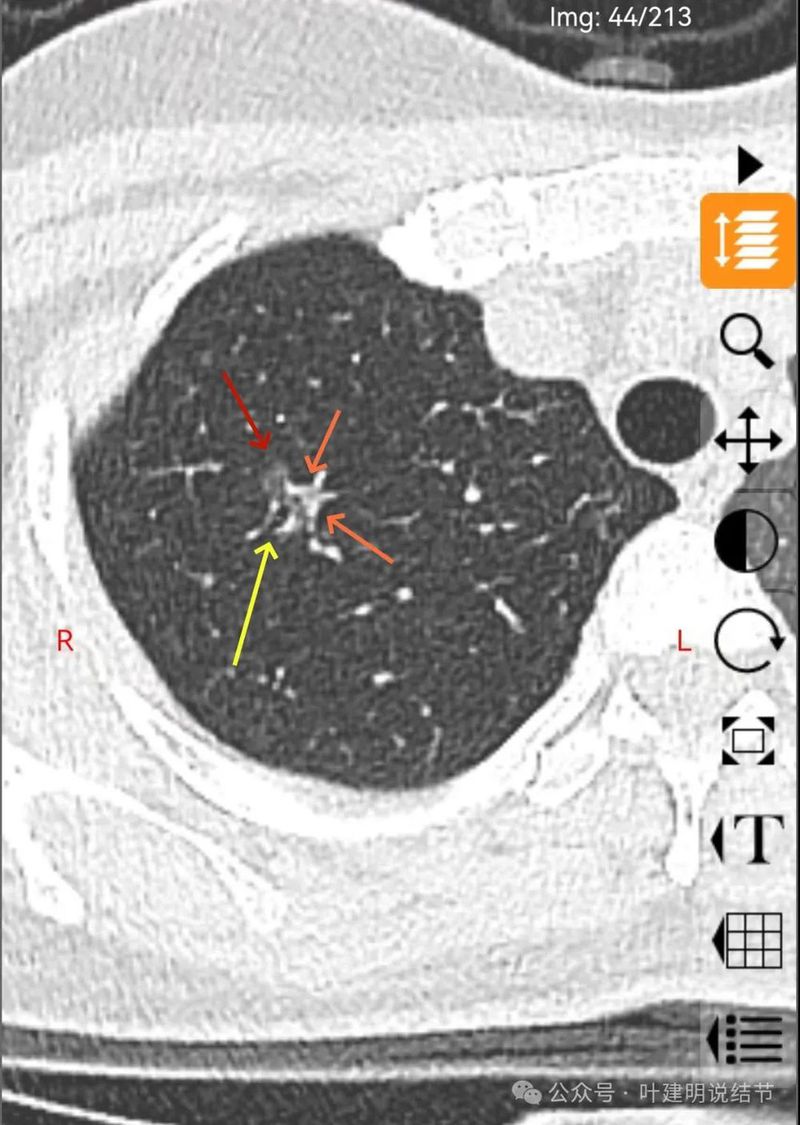

病灶密度稍不均,分叶明显,中间有扩张的细支气管,血管有贴边。整体轮廓与瘤肺边界清。

分叶状明显,支气管扩张明显,血管弯征可见,整体轮廓清。

灶内支气管扩张,附近血管有异常增粗,表面不平。